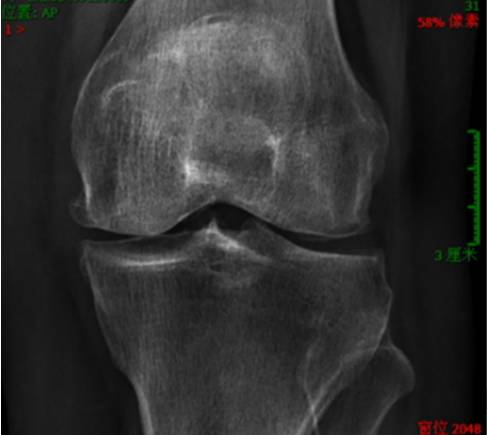

前几天,六十岁的张阿姨来门诊看病,向我诉说膝关节疼痛的苦恼。张阿姨家住3楼但没有电梯,早晚要步行接送孙女上上学,还操持家里的一日三餐,本来身体一直还不错,只是膝盖屈伸活动时感觉到弹响,但近5年来开始出现上下楼时膝关节疼痛,走平路还可以,到了最近半年竟然走平路也会膝关节疼痛了,上厕所时蹲起十分困难。张阿姨到附近医院拍了膝关节X片,报告写的是关节退变、骨质增生、关节间隙变窄,诊断为 双膝骨性关节炎 ,为求中医治疗来找我看病。这个病就是我们今天要说的膝骨关节炎,也是膝关节疼痛最常见的原因之一。

骨关节炎又称退行性关节病、增生性关节炎等,一般认为是一种以软骨变性、破坏及骨质增生为特点的关节病,但实际上其也存在关节炎症并可以累及整个关节。膝关节是骨关节炎最常见的发病部位之一。

临床症状常表现为关节疼痛和功能障碍,早期表现为劳累、负重或上下楼时加重,可伴肿胀及轻度晨僵。随着病情发展,可出现关节疼痛加重,关节变形,如“O”型腿、“X”型腿。疾病晚期关节严重变形,可导致行走困难,严重影响生活质量。